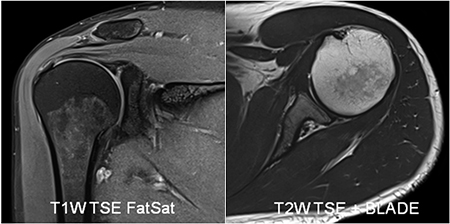

<SIEMENS社製MAGNETOM skyra3.0テスラ(T)MRIのご紹介>

3.0テスラの強い磁場で検査することにより、より強い信号が得られるため情報量が多く、より高分解能(高画質)な画像、より短時間撮影が可能となりました。

多彩な専用コイルで高画質

頭部や脊椎、乳房専用コイル、肩関節専用、膝関節専用、手指関節専用など撮像部位に応じた多彩なコイルを用意しています。

[造影両乳房撮像例]

[肩関節撮像例]

[膝関節撮像例]

[腰椎・腰髄撮像例]